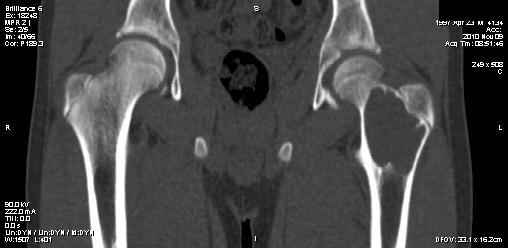

Мальчик 13 лет. В течение нескольких месяцев беспокоят боли в левом тазобедренном суставе.

При обследовании выявлена киста шейки левого бедра с сопутствующими изменениями в головке бедра, которые мы трактуем как дистрофические. Планируем вскрытие и санацию полости кисты передне-боковым доступом, костную пластику. Перед нами возникли следующие вопросы: для пластики использовать крыло подвздошной кости либо большеберцовую кость,либо их комбинацию, (полость большая,одним крылом можно не обойтись) или донорский аллотрансплантат с Коллапаном? Фиксировать ли? Если фиксировать, то чем? Доступны обычные угловые пластины либо АВФ.